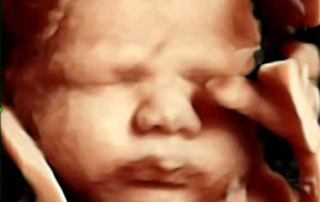

סקירת מערכות

סקירת מערכות אצל מומחה יכולה לזהות עד 90% מהמומים הקיימים בעוברים. מומלץ לקבוע תור מראש על מנת שלא לפספס את חלונות הזמן.